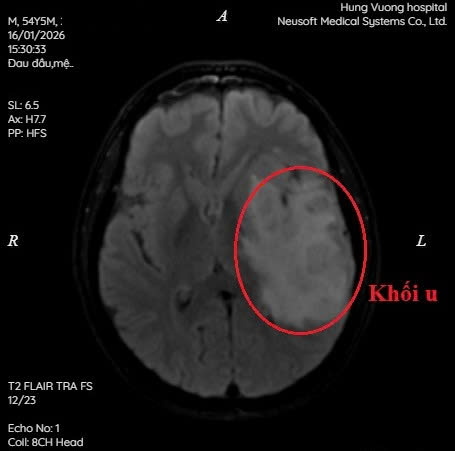

Kết quả MRI cho thấy

• Nhiều khối tổn thương tại thuỳ trán và thuỳ thái dương trái, kích thước lớn nhất khoảng 32 x 46 mm

• Ngấm thuốc không đồng nhất sau tiêm, kèm phù não mức độ vừa

• Gây hiệu ứng khối, đẩy lệch đường giữa sang phải khoảng 7 mm

Hình ảnh gợi ý theo dõi u thần kinh đệm bậc cao đa ổ, một bệnh lý nguy hiểm, tiến triển nhanh, có thể ảnh hưởng trực tiếp đến tính mạng nếu chẩn đoán muộn.